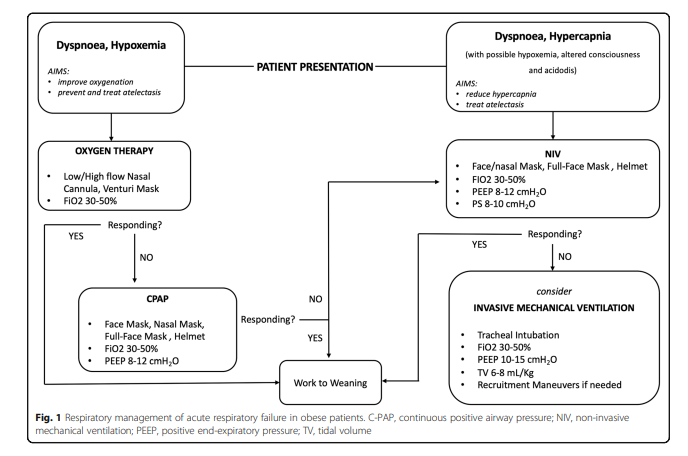

🔐This new randomised trial from Dr Giuseppe Pascarella suggests the PENG block is an effective opioid sparing analgesic technique that allows early postoperative mobilisation. Worth considering as a valid analgesia option for fast-track hip surgery protocols? 🔗…-publications.onlinelibrary.wiley.com/doi/10.1111/an…

Two recent comparative trial supporting PENG block for hip arthroplasty Randomized comparison between pericapsular nerve group (PENG) block and suprainguinal fascia iliaca block for total hip arthroplasty rapm.bmj.com/content/early/… …-publications.onlinelibrary.wiley.com/doi/epdf/10.11…